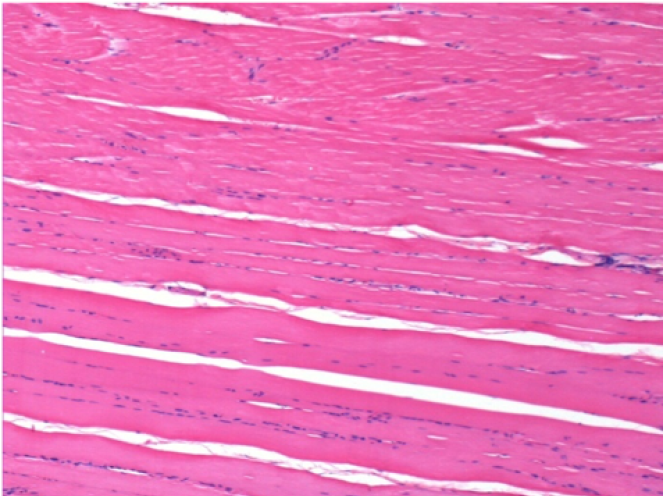

1 month after Endopeel Injection 0.1ml in the right pretibial muscle.

What is seen in black on the pictures is not a necrosis like could imagine some scientifics !

In fact, 4 conclusions have to be taken in consideration